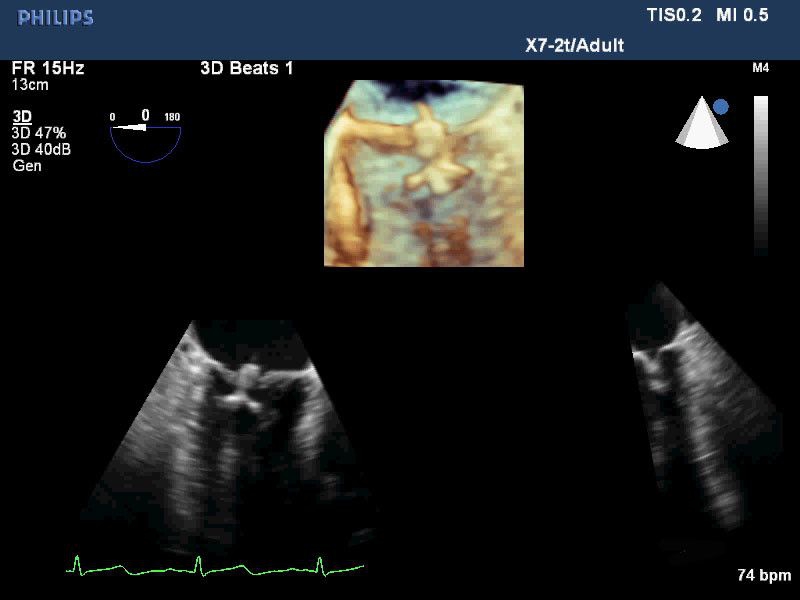

• Live 3D TEE: Эта функция позволяет проводить чреспищеводную эхокардиографию в режиме реального времени, что позволяет оценить механические сокращения сердца с точностью, необходимой для оценки результатов хирургического вмешательства.

• Live xPlane: Эта функция позволяет одновременное отображение в двух плоскостях, что обеспечивает более полную информацию для диагностики.

• Чреспищеводный УЗИ датчик Philips Х7-2T